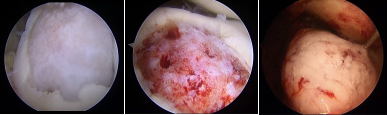

镜下软骨缺损区域——软骨缺损区域清创+微骨折术——镜下局部注射胶原蛋白软骨修复支架

经科室讨论、详细评估,并获得小魏及其家长同意后,日前,由赵其纯主刀,为他成功实施了胶原蛋白软骨修复支架诱导自体软骨成形关节镜手术。在关节镜监视下,医生精准定位到缺损区域,对缺损区域进行清理、二氧化碳枪吹干,随后将液体的胶原蛋白软骨修复支架注射植入到受损部位,并配合微骨折技术,刺激促进自体软骨再生。

本次术中使用的胶原蛋白软骨修复支架由猪源I型胶原蛋白凝胶构成,能给软骨细胞提供一个可以附着和生长的地方,配合微骨折技术能诱导、刺激身体自身的软骨细胞慢慢再生,修复膝关节的软骨缺损。